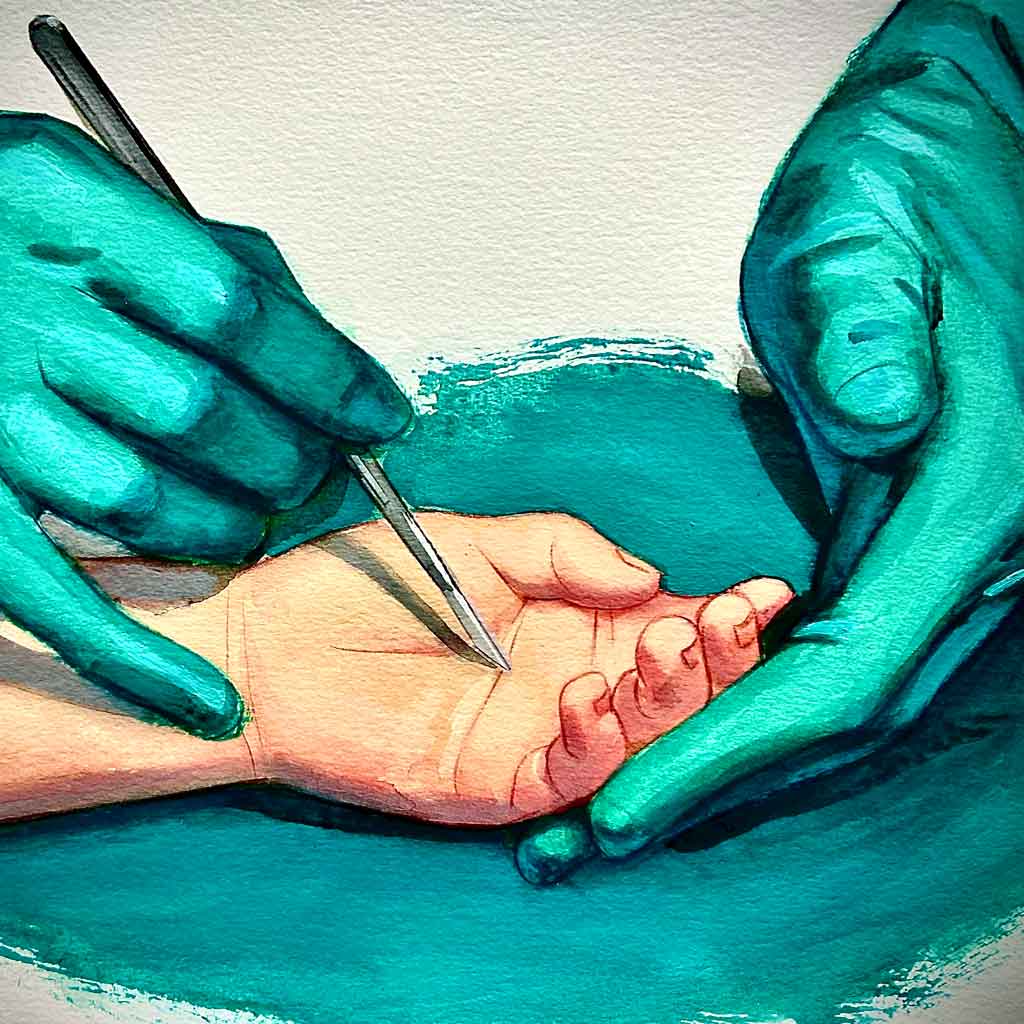

Cirugía de la rizartrosis

La cirugía de la rizartrosis está indicada en casos avanzados; cuando el dolor y la limitación funcional no responden a los tratamientos conservadores.

En nuestra Unidad realizamos tres técnicas quirúrgicas para la rizartrosis: